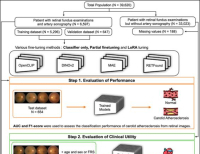

- 제이엘케이, 비조영 CT 기반 뇌경색 병변 검출 AI 성과 논문 게재 … 손상범위 정량화, 예후예측 가능

- 의료 AI 전문기업 제이엘케이가 개발한 뇌경색 병변 검출 AI 모델이 대규모 임상 검증을 통해 신뢰성을 입증했다.이번 성과는 SCI급 국제학술지 ‘Frontiers in N...

- 2025-09-11